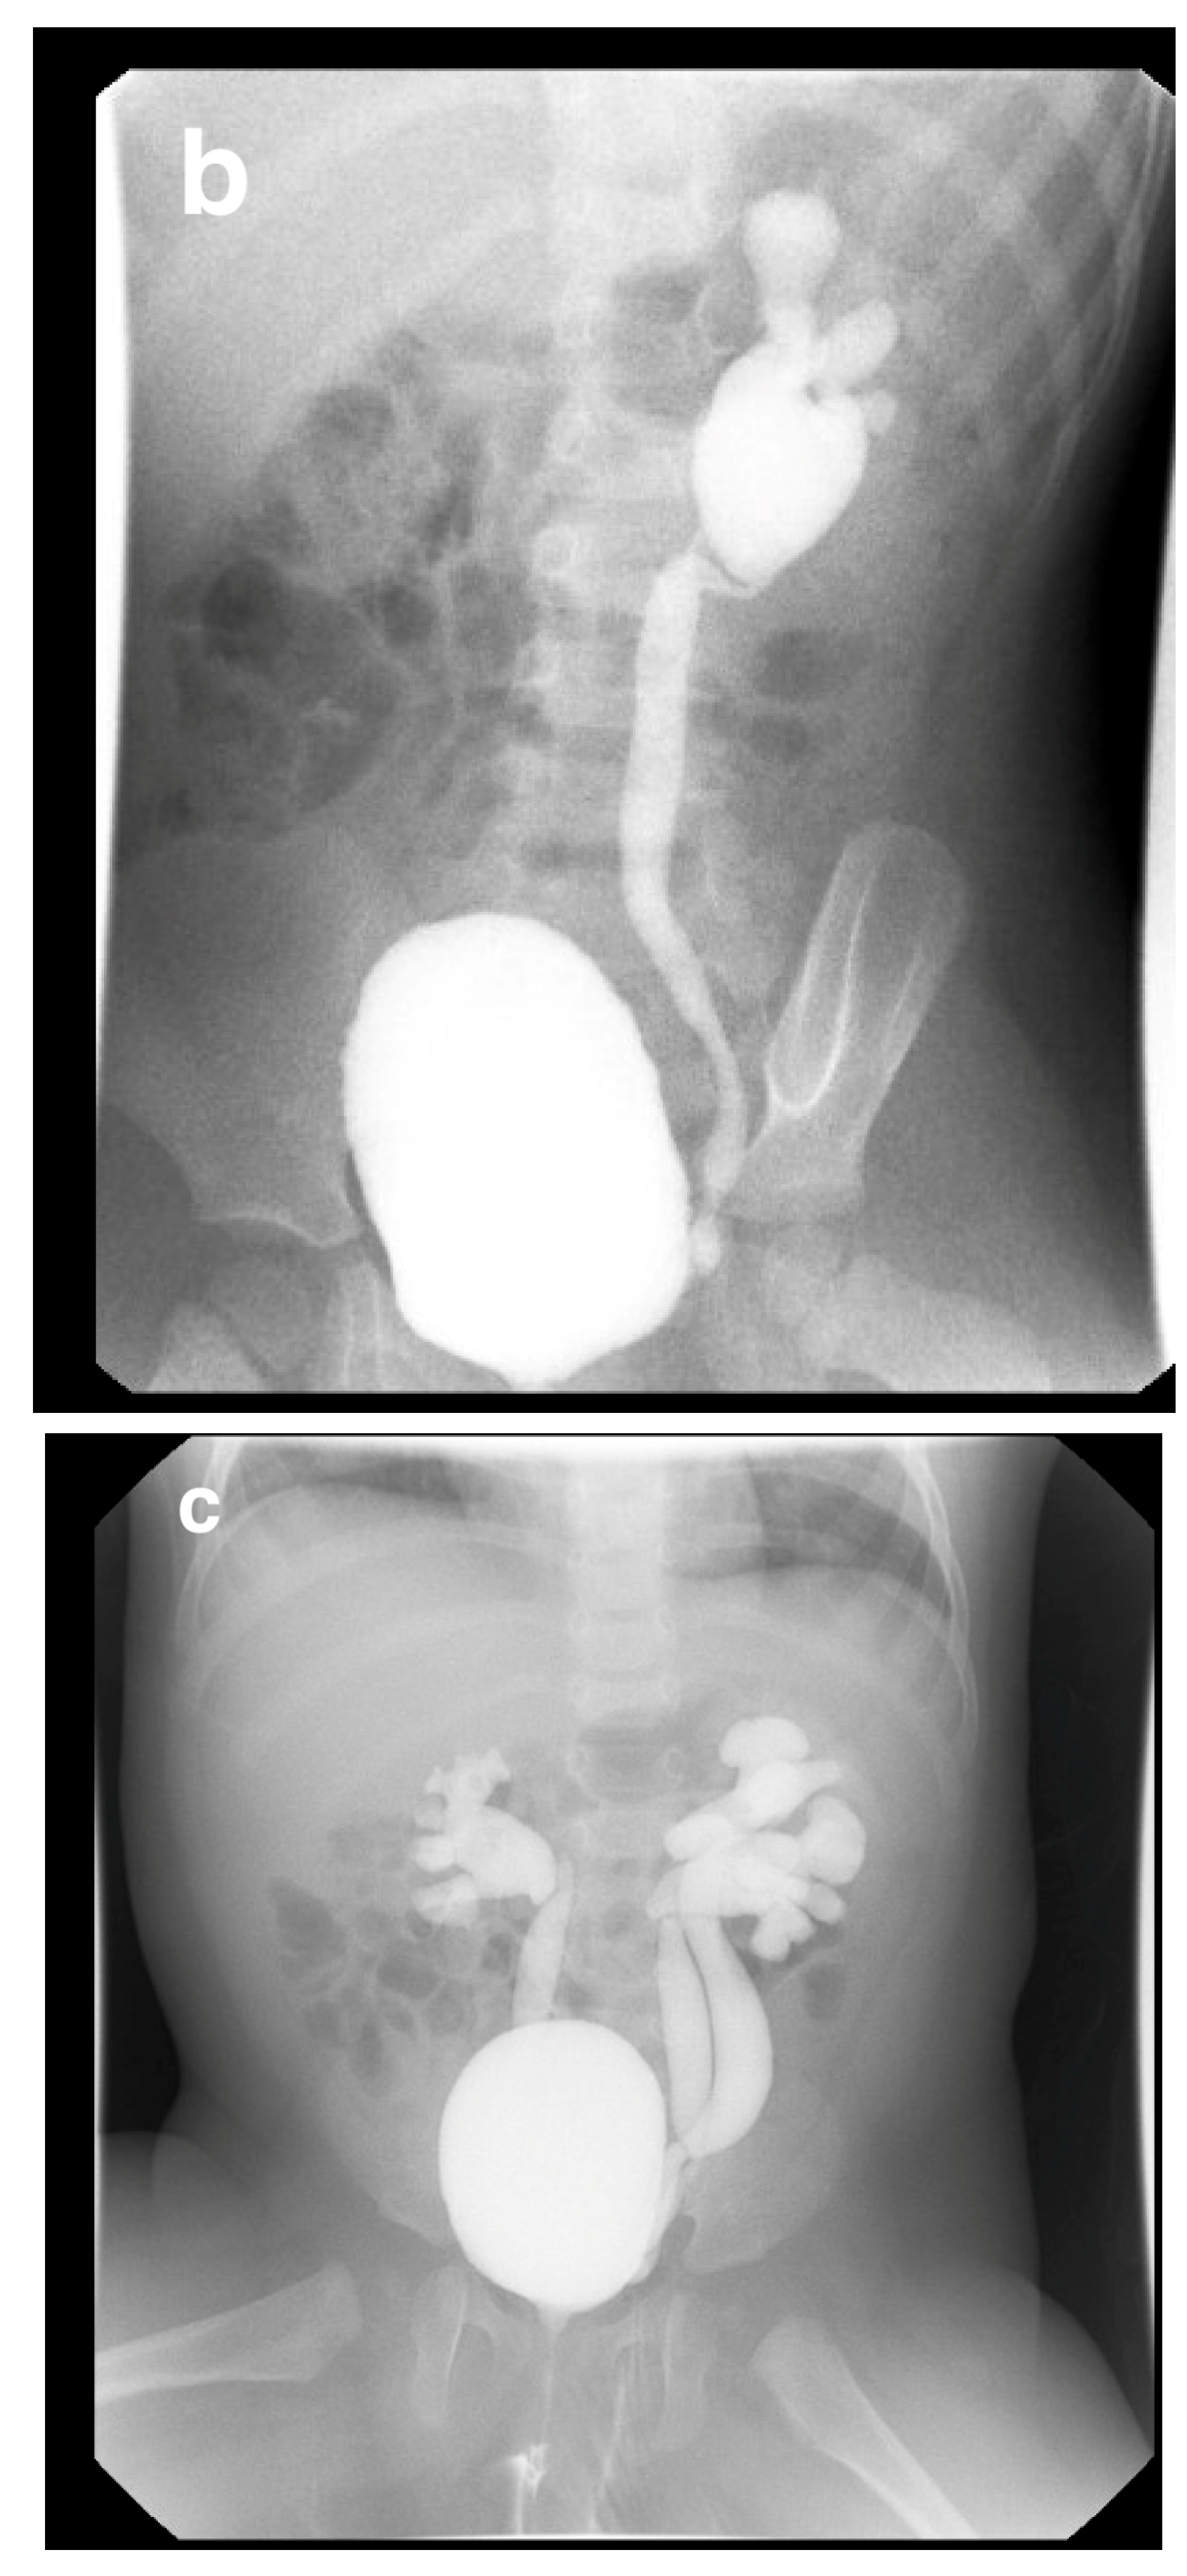

14. Duplex Collecting System

16. Vesicoureteral Reflux